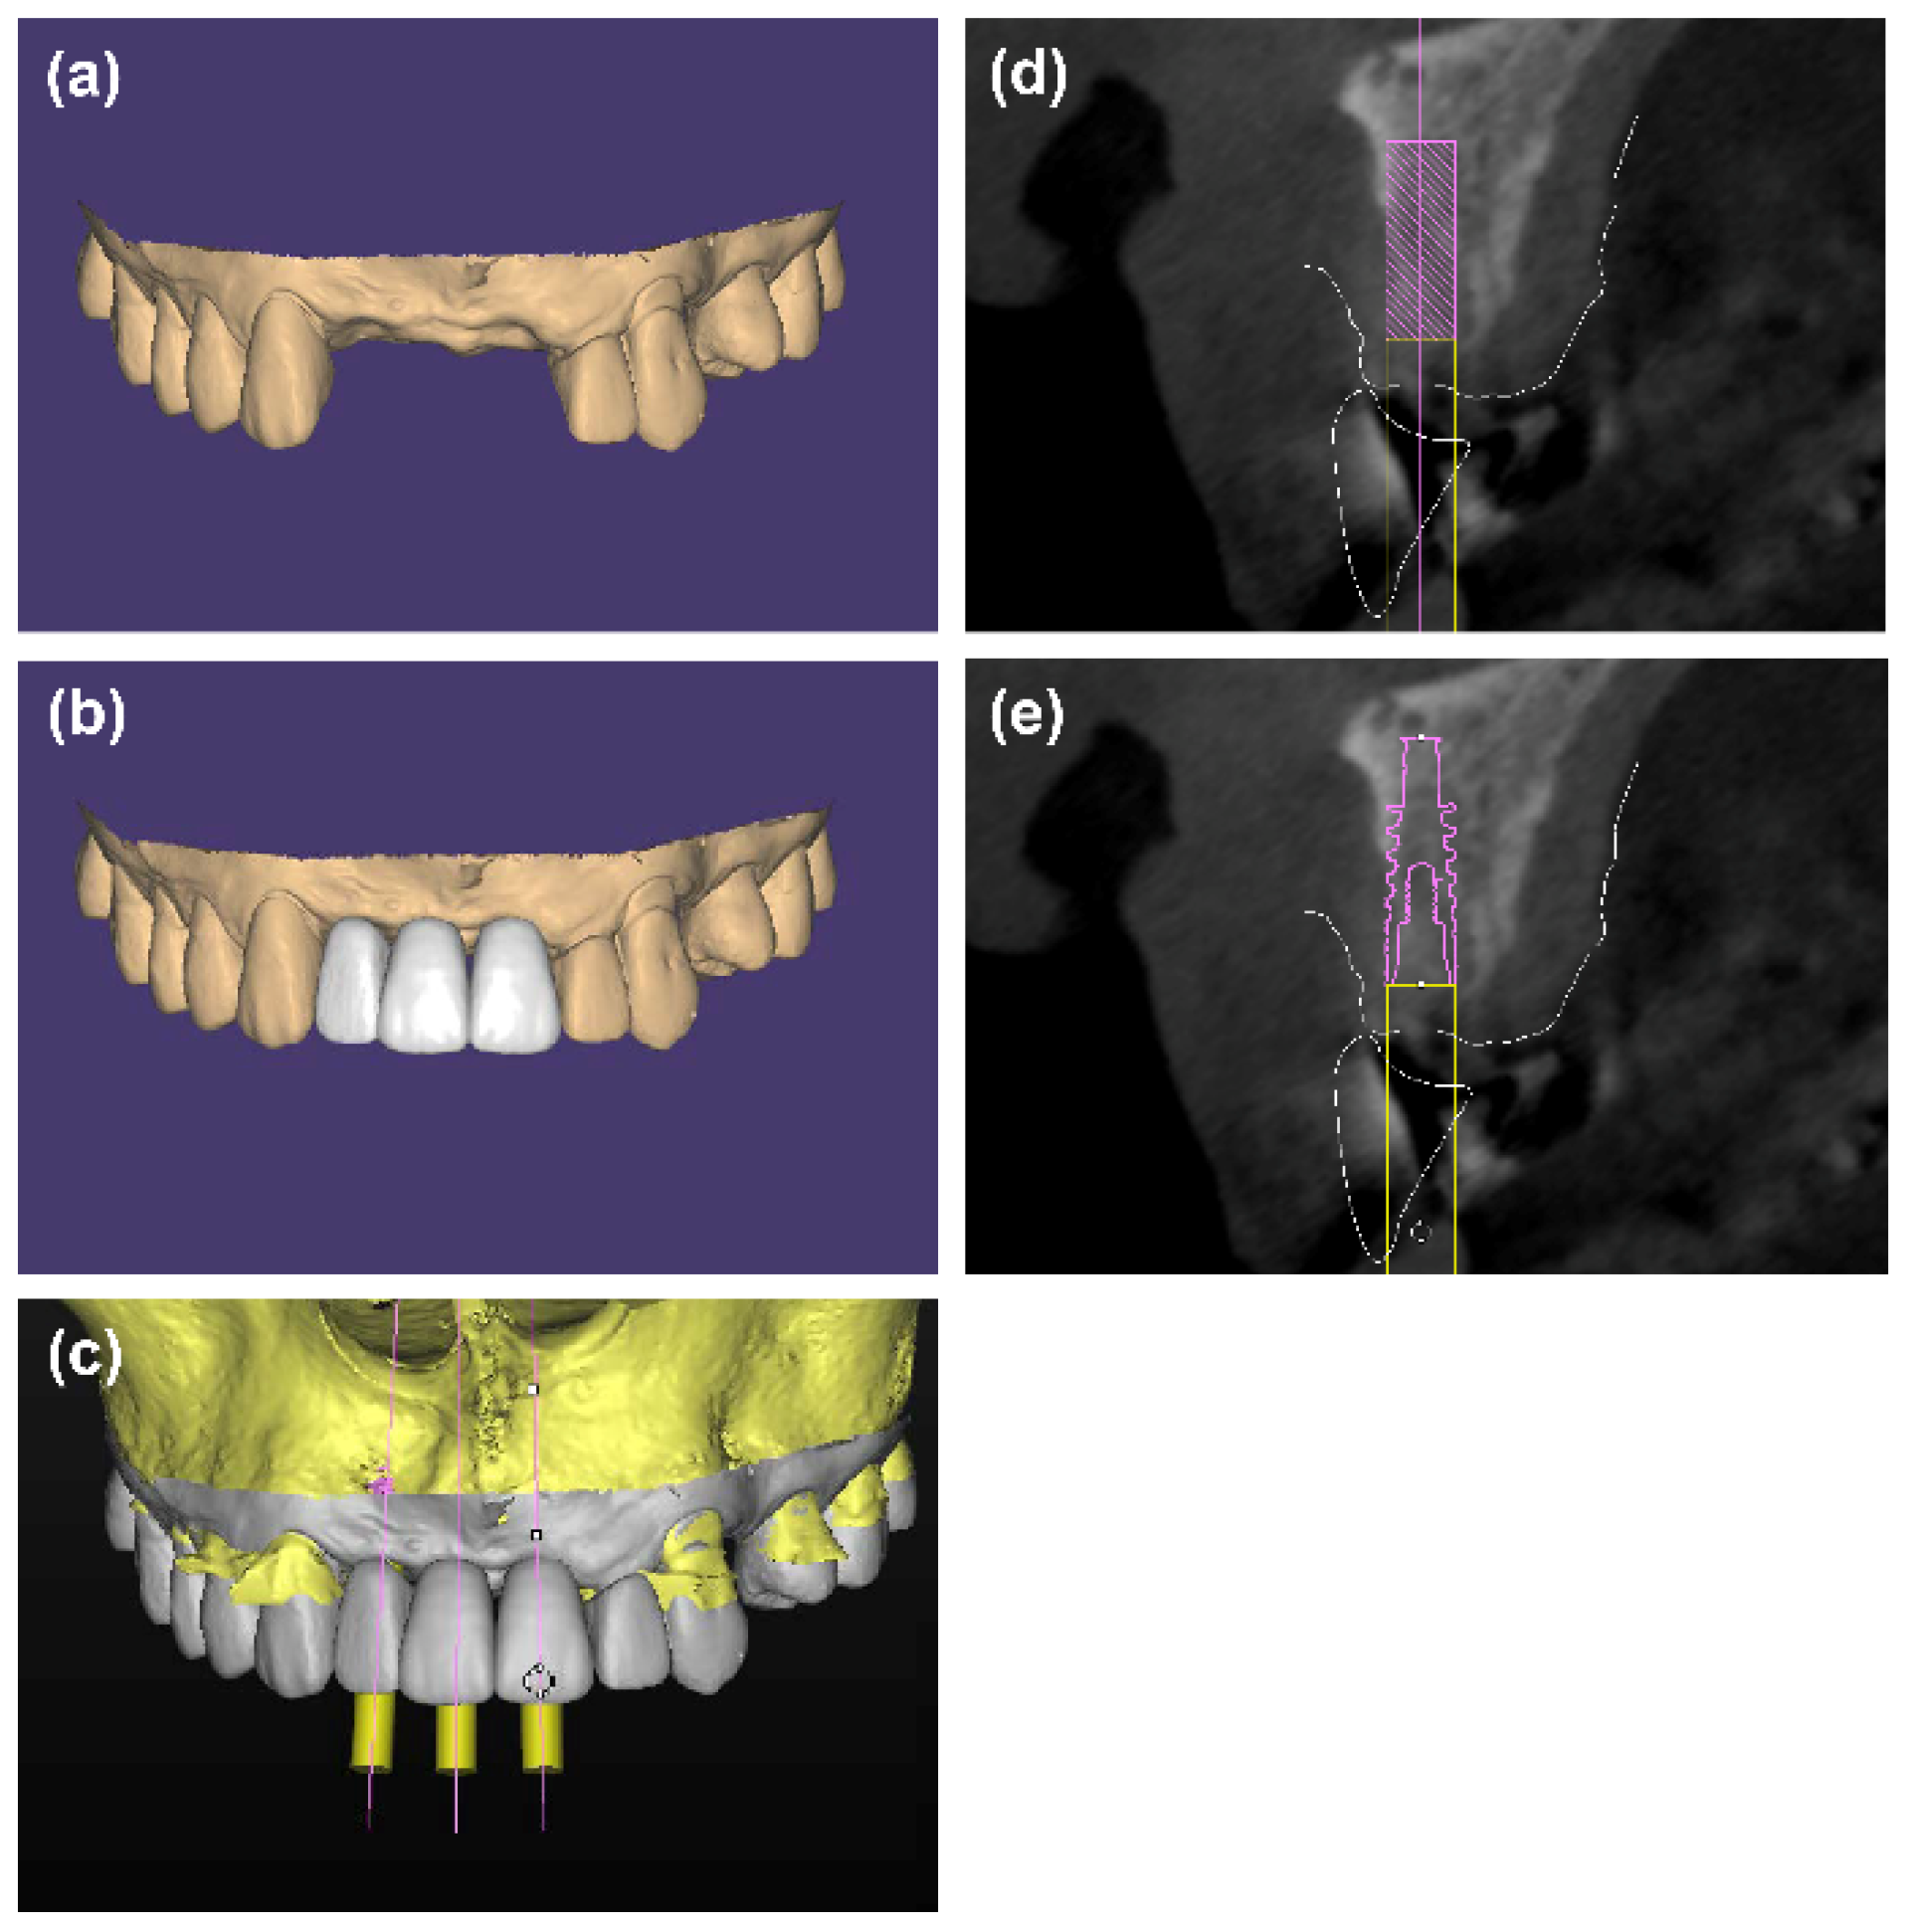

:1. Introduction

2. Materials and Methods

2.3. Radiographic Evaluation